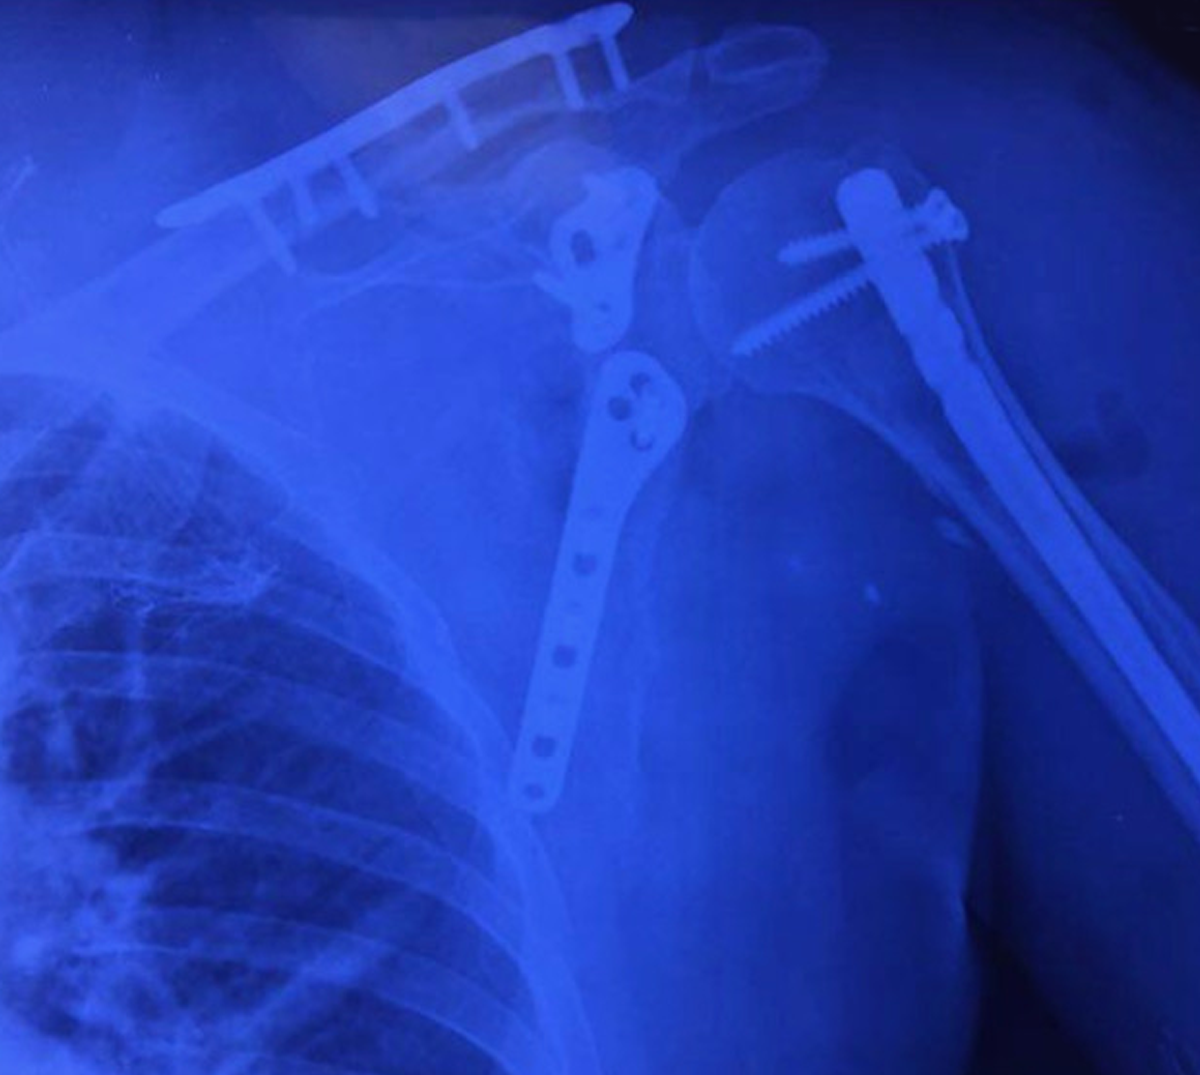

REEMPLAZO ARTICULAR

(HOMBRO, RODILLA Y CADERA)

Las prótesis son implantes ortopédicos que se colocan en el cuerpo con la finalidad de sustituir a una articulación lesionada.

De forma común, sus indicaciones son por secuelas de osteoartrosis, artritis reumatoide y fracturas en algunos casos.